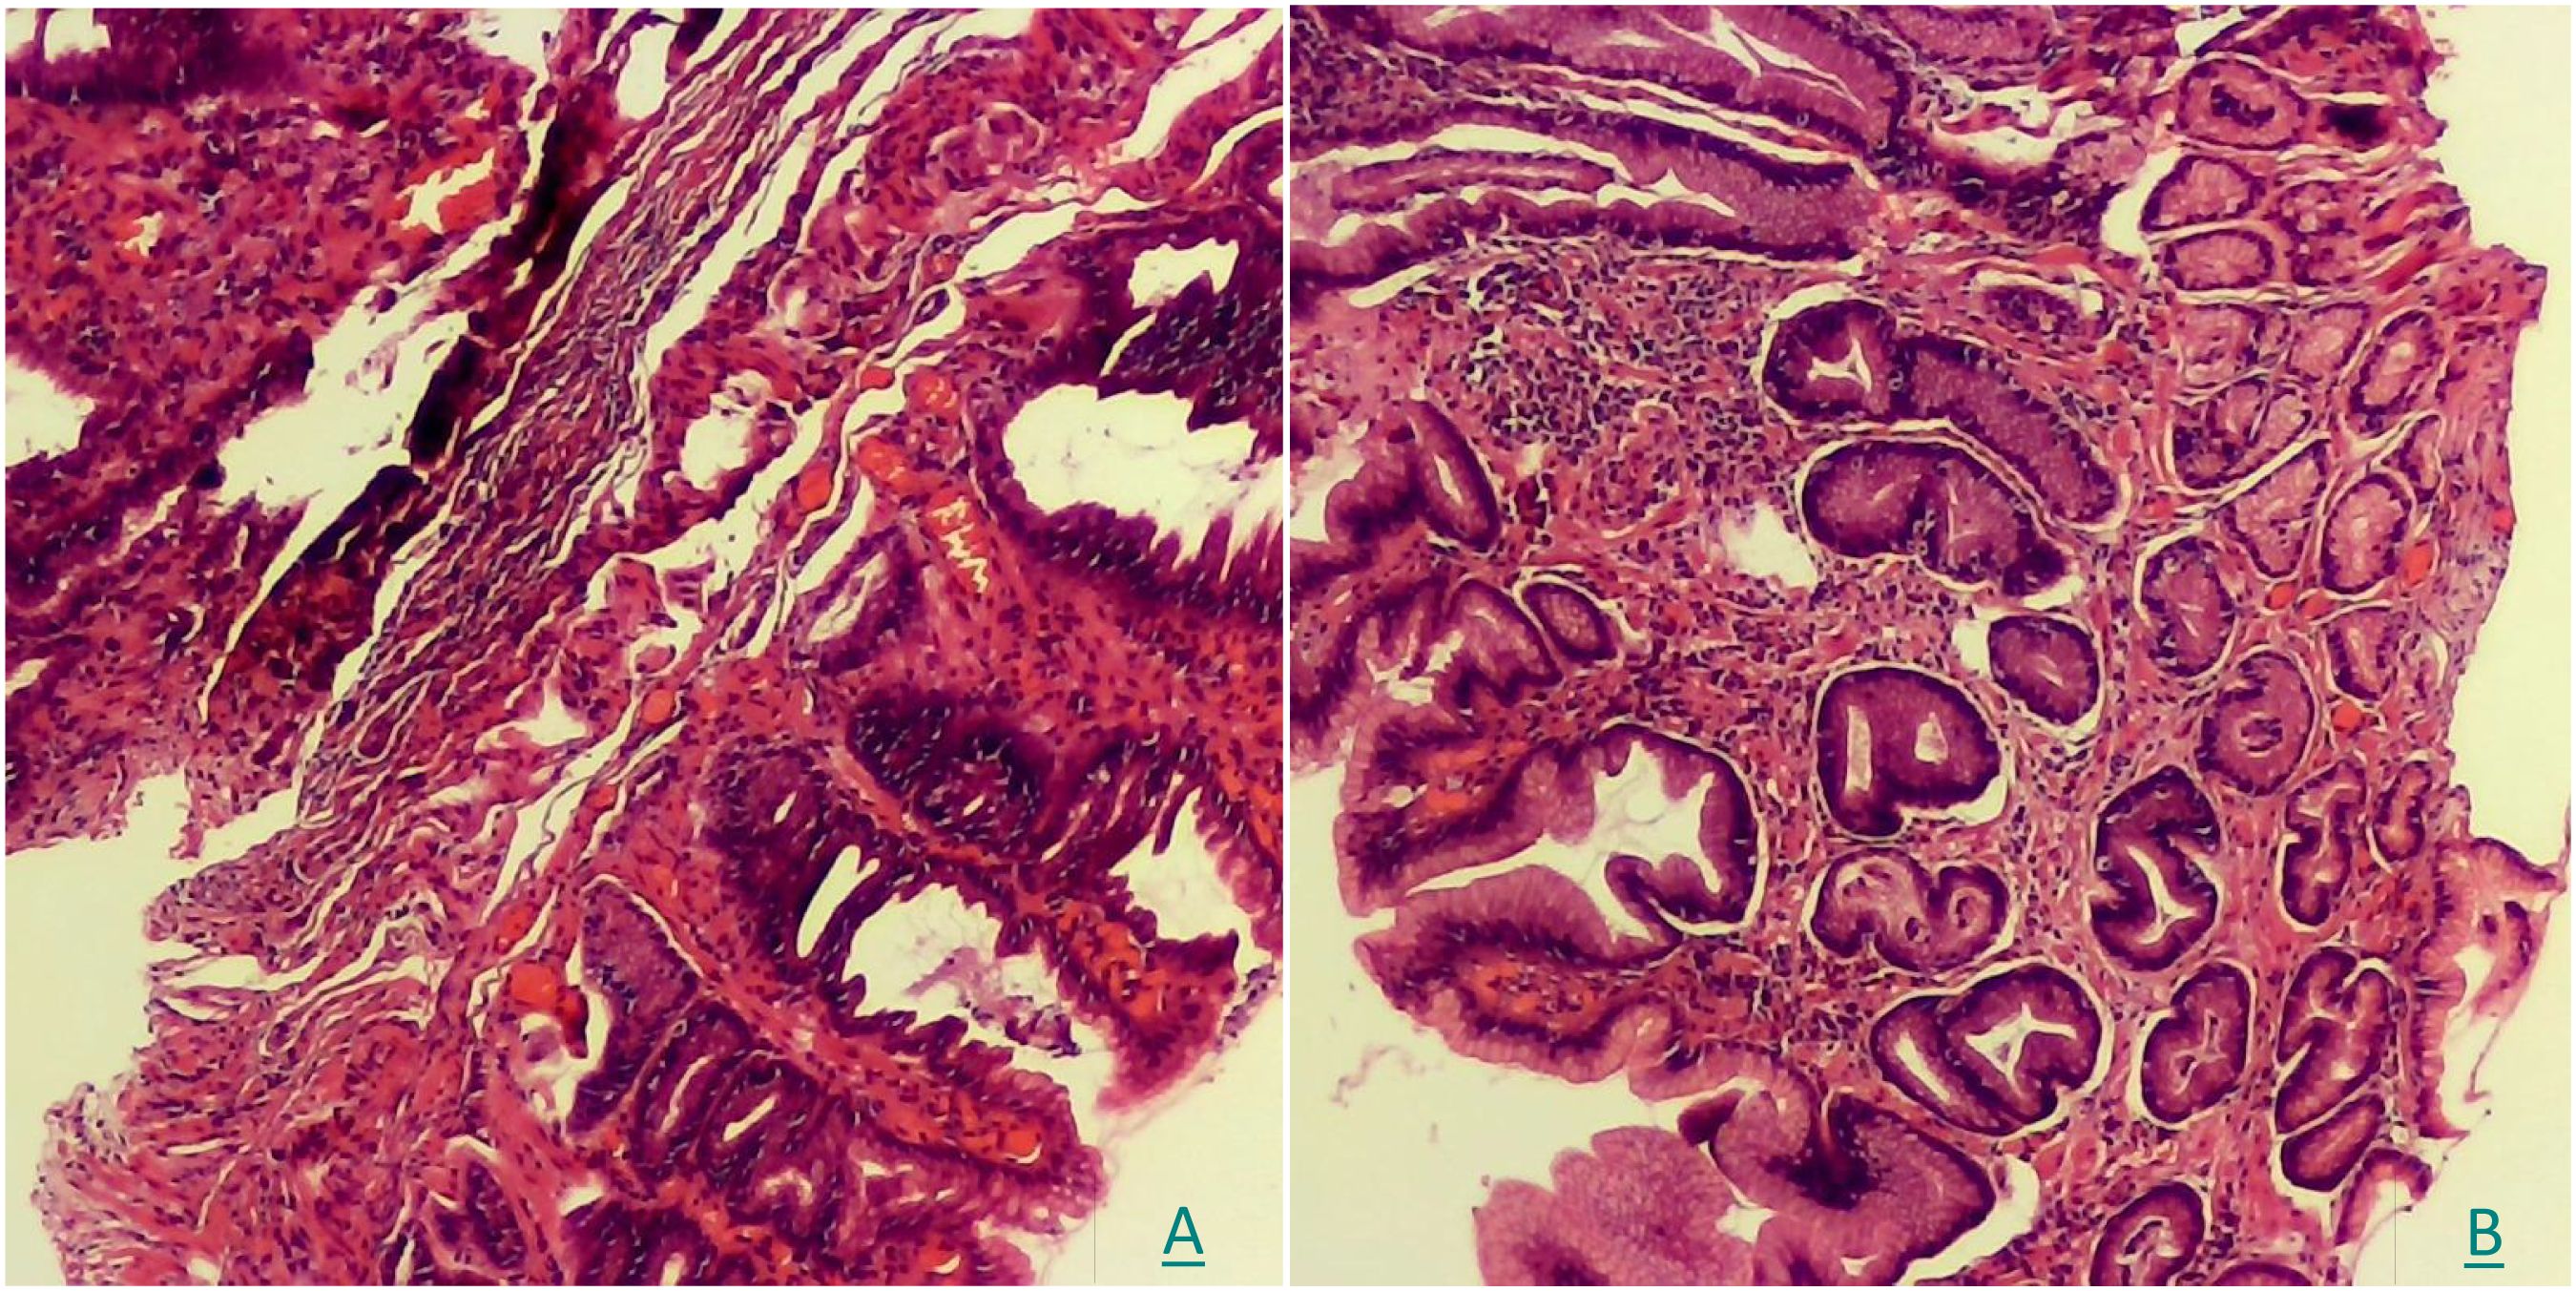

A histopathological analysis was conducted using the biopsy samples when the CLE was performed. The examination confirmed moderate mucosal inflammation (activity+++) with hyperplastic polypoid changes and reactive glandular alterations (Figure 4).

Figure 4. (A, B) The pathological examination of HE staining showed moderate mucosal inflammation (activity+++) with hyperplastic polypoid changes and reactive glandular alterations.